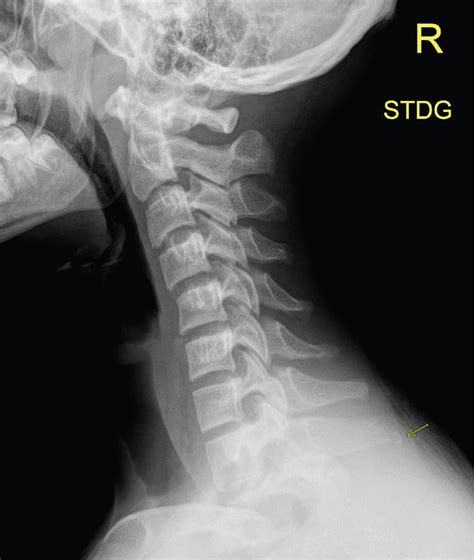

Diagnosis of Clay Shoveler's Fracture

Diagnosing a Clay Shoveler's Fracture involves a combination of physical examination and imaging tests. The diagnostic process typically includes:

• Imaging Tests:

• X-rays: To visualize the fracture and assess the extent of the injury.

• CT Scans: For a more detailed view of the bone structure and to rule out other injuries.